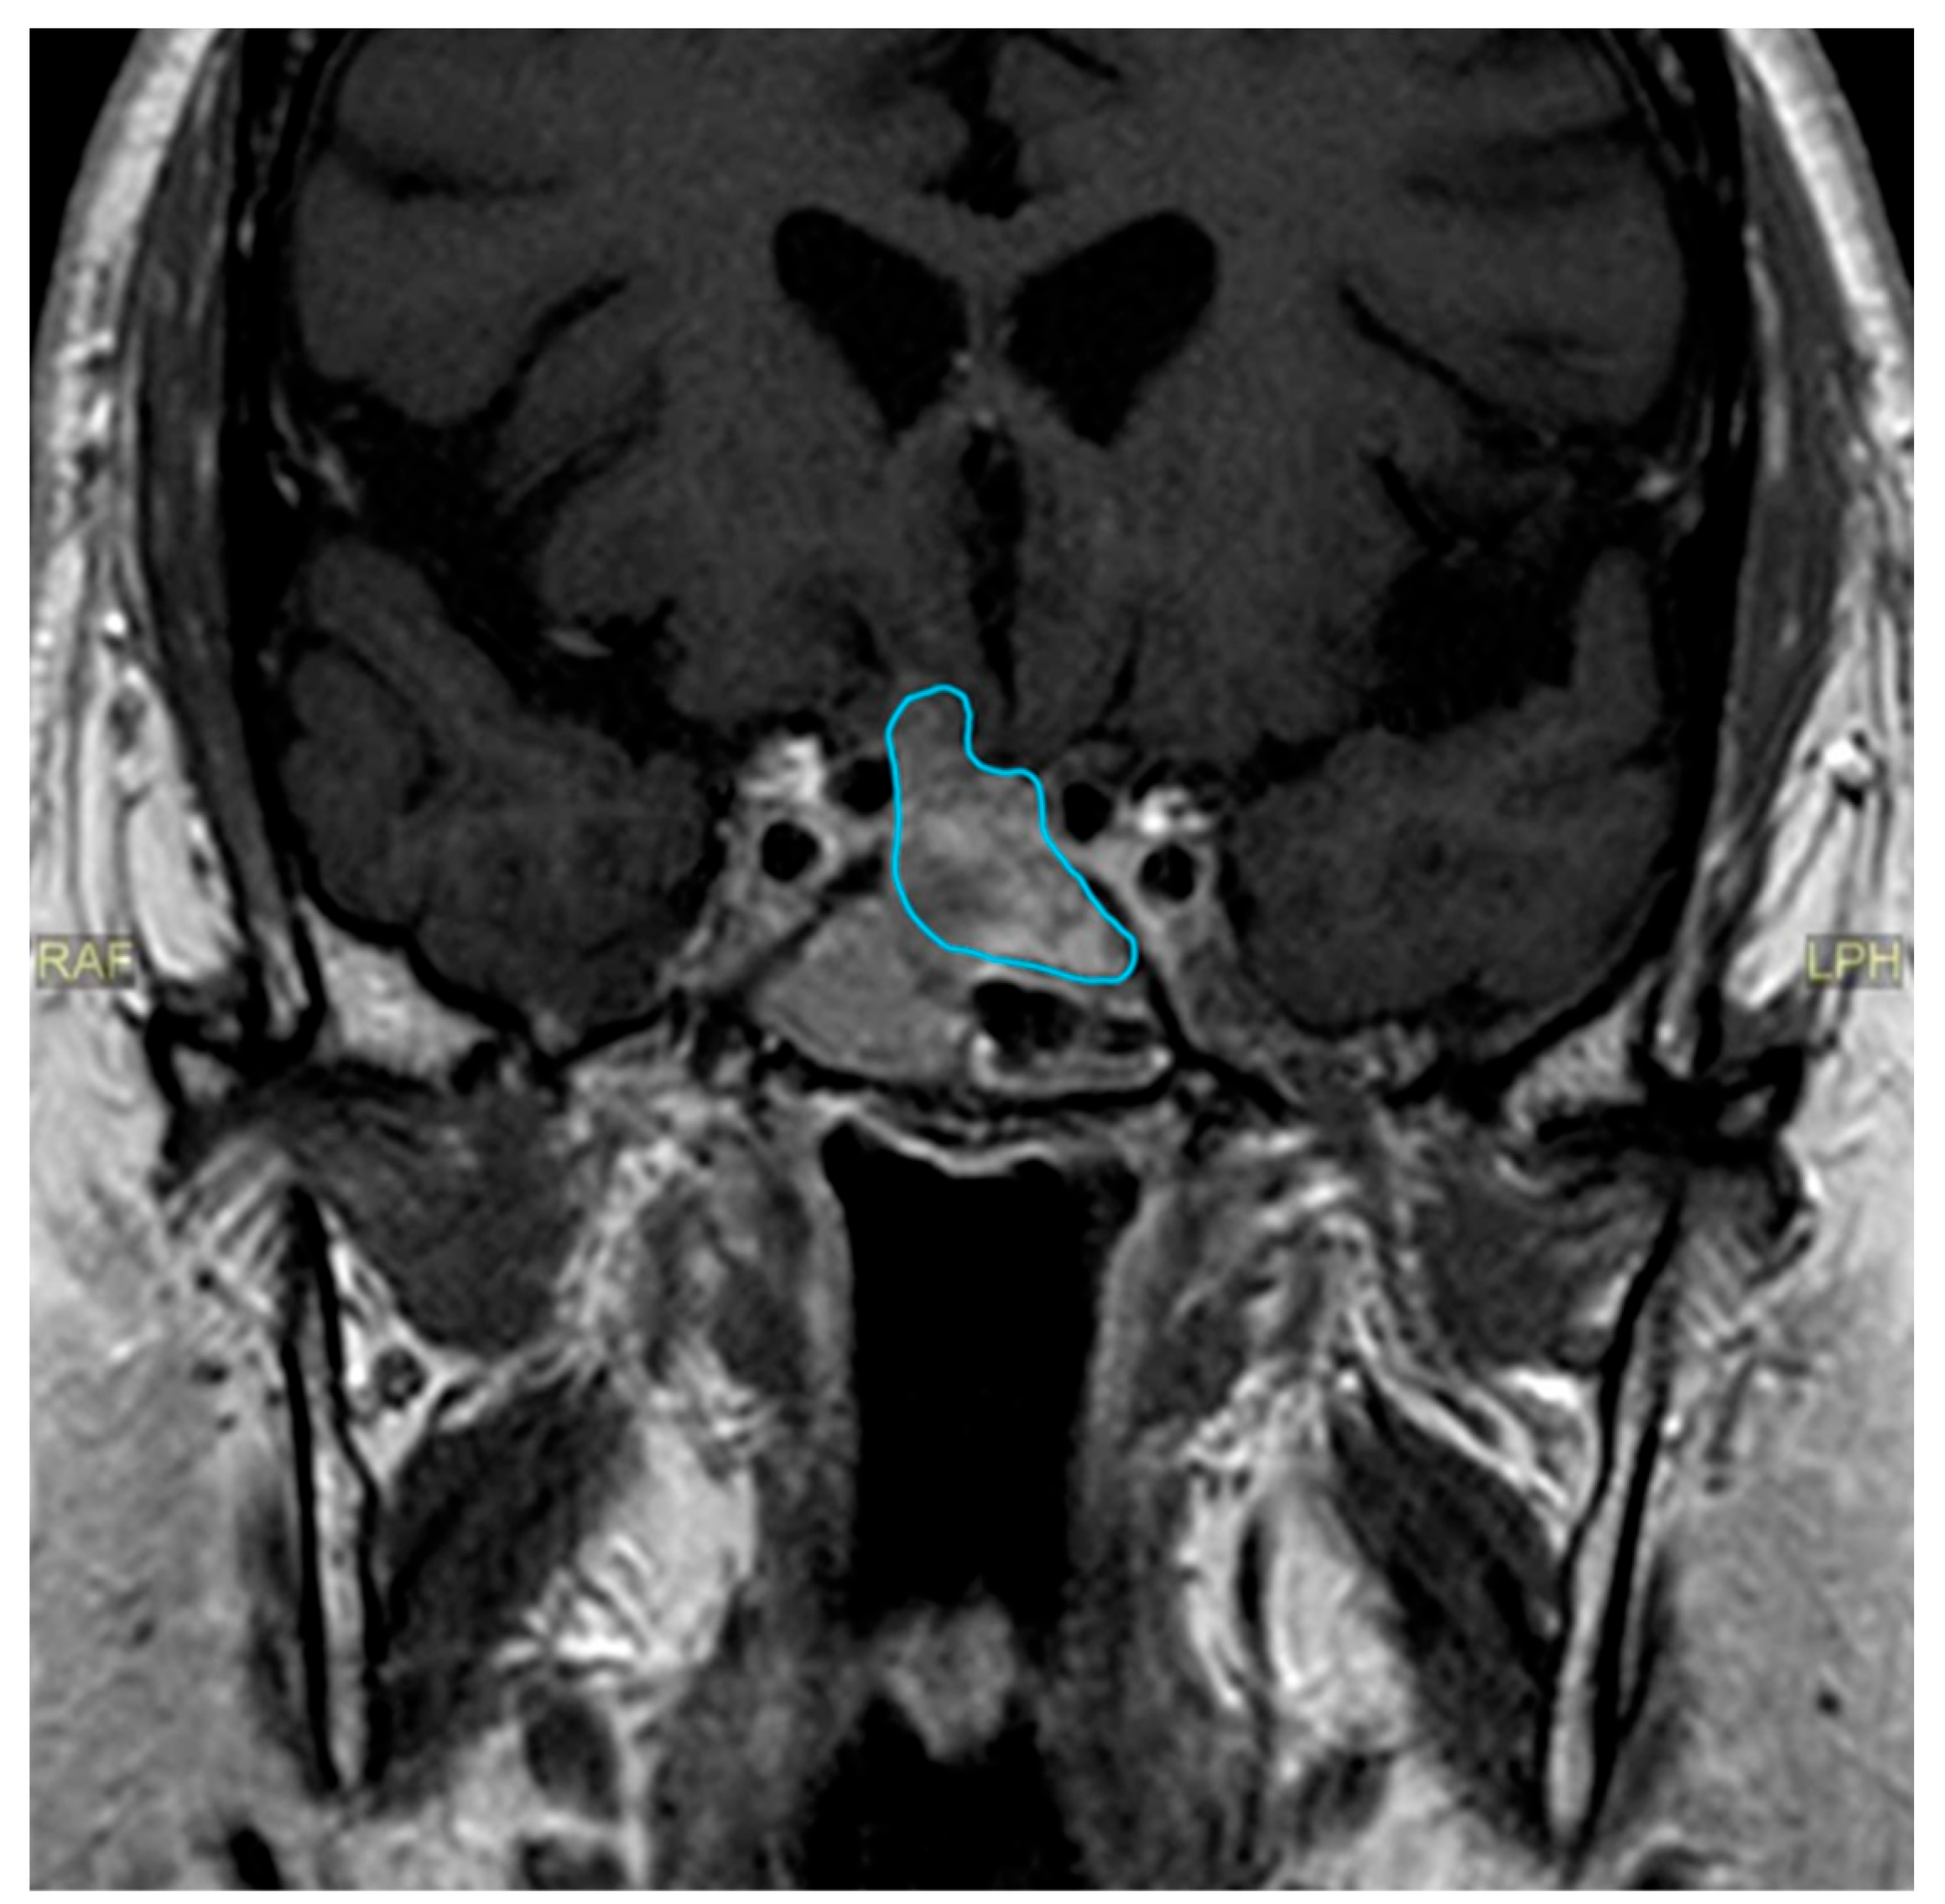

| Date | July 2018 | January 2019 | July 2019 | June 2020 | October 2020 | December 2020 | June 2021 |

|---|---|---|---|---|---|---|---|

| Prolactin (ng/mL) | 22.1 | 27.6 | 71.2 | 681.9 | 0.4 | 1.8 | |

| MRI | Macroadenoma (20 × 20 × 18 mm) with signs of pituitary apoplexy. Invasion of the optic chiasm, hypothalamus, and the left cavernous sinus. | 5 × 2 mm nodular structure that could be related to remnant glandular tissue. Persistent left deviation of the pituitary stalk. | Tumor growth (16 × 14 × 11 mm). Significant compression of the optic nerve and the optic chiasm. | Discrete decrease in volume of the tumor (13 × 12 × 8 mm). No compression of the optic nerve and the chiasm. | Volume reduction (13 × 10 × 6 mm). The structure is no longer in contact with the gyrus rectus and the subcallosal area. | ||

| Treatment | First surgical procedure | Second surgical procedure | Cabergoline started |